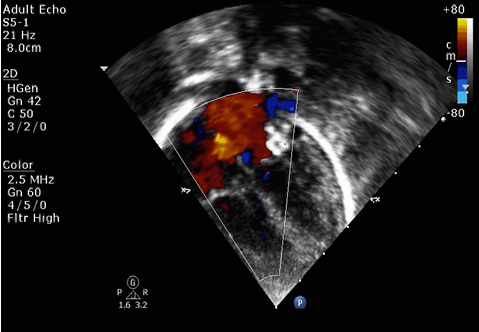

梅*,37岁,G2P1,孕27周首诊,分别于31周、35周随访 ,胎儿心彩超诊断:左冠状动脉右房瘘、右房右室增大、冠状窦增大、少量心包积液。孕35+3周剖宫产一男婴,出生体重2750g,生后心彩超诊断:左冠状动脉-右房瘘、动脉导管未闭、肺动脉高压 。生后立即送入NICU监护,立即予心彩超检查,生后第5天予左冠状动脉-右房瘘介入封堵术,即使用介入的方法将封堵器放置于心房的瘘口处。手术成功,患儿瘘口处无分流。